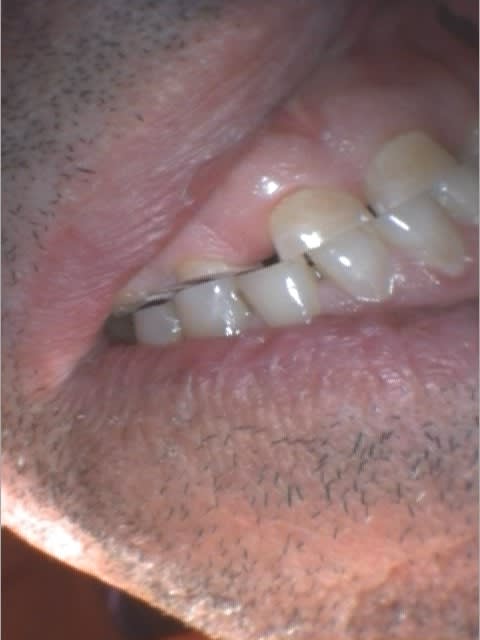

Là en même temps, j'ai remonté ma DVO, et je laisse comme ça quelques jours pour tester...

Le meilleur articulateur c'est la bouche... non? :-)

Quelques remarques :

1 - les dents étaient encore vivante malgré l'importante de l'abrasion. Cela prouve que la pulpe est une bonne obturation, non? J'ai fait les endo du bloc incisivo canin hier, et les provisoires ce matin.

2 - Quand il n'y a plus de calage postérieur, ça le part pas toujours en éventail : théorie du maillon faible... Si le parodonte est faible, ça part en éventail, si les dents sont longues et le parodonte solide + éventuellement occlusion en bout à bout, c'est les dents qui s'usent...